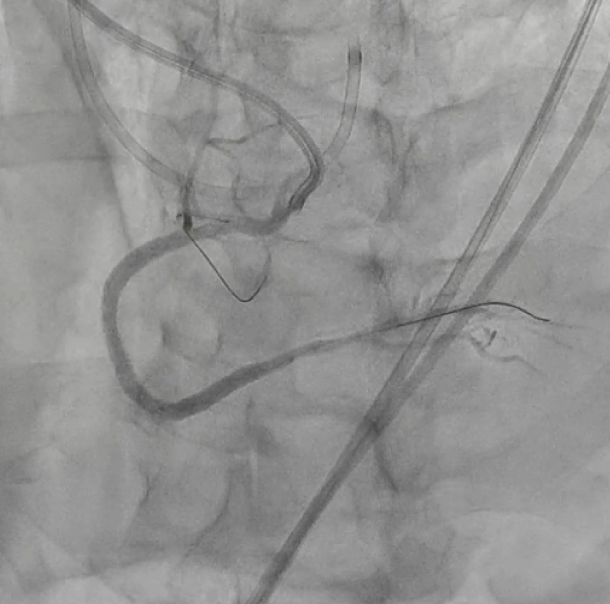

An 8Fr guiding catheter was inserted intothe RCA from the right femoral artery. By performing the anchor balloontechnique, the guiding catheter became stable, and guidewire was advanced intothe occluded lesion. However, due to insufficient information of the distallesion, we switched to a retrograde approach to improve distal visualization.Tip injection through the microcatheter at the third septal branch showed aconnection to the distal RCA, and the floppy wire passed through to Seg4PD. Theretrograde wire which reached the distal end of the lesion was used as amarker, and the antegrade intermediate wire could be passed through the occludedlesion using the kissing wiring technique. After intravascular ultrasound observation,a drug-eluting stent was implanted from RCA distal to proximal, and normalantegrade blood flow was achieved.

We report a case in which revascularizationwas performed using a retrograde approach in the subacute phase of an acute inferiormyocardial infarction. Anatomical features such as the forward origin of theRCA and the coronary tortuosity made revascularization difficult using only theantegrade approach. The procedure was completed successfully by an anchorballoon technique and a distal visualization via a retrograde wire. Even in theacute phase of myocardial infarction, it is important to consider a retrogradeapproach if necessary.